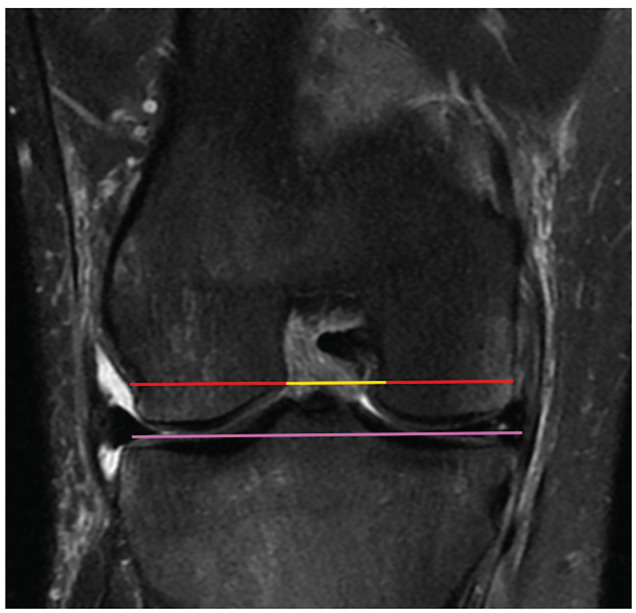

Methods: Patients ≥14 years of age with a confirmed ACL injury on MRI were included for review. Two orthopaedic resident physicians measured the NWI using both axial and coronal cuts using previously described measurement criteria as well as a modification utilizing the MRI cuts with the widest bicondylar width. The NWI was computed and a t test was performed to compare the axial and coronal measurements. Interobserver reliability was assessed using 2-way mixed intraclass correlation coefficients (ICCs).

Results: A total of 64 patients with ACL injuries were included. Modified axial and coronal NWIs for the cohort were a mean ± SD of 0.27 ± 0.02 and 0.23 ± 0.02, respectively. Modified axial NWIs were greater than coronal NWIs (P < .001). Standard axial and coronal NWIs for the cohort were 0.29 ± 0.03 and 0.25 ± 0.03, respectively. Standard axial NWIs were greater than coronal NWIs (P < .001). Modified axial and coronal NWIs for male and female patients were not different (P = .61 and P = .14, respectively). Axial notch width measurements were greater than coronal notch widths for both modified and standard measurements (P < .001). Axial intercondylar distances were not different from coronal intercondylar distances for both standard and modified measurements (P = .06 and P = .22, respectively). The ICCs for modified coronal and axial NWIs were 0.88 and 0.97, respectively. The ICCs for standard coronal and axial NWIs were 0.99 and 0.99, respectively.

Conclusion: NWIs were greater when measured on an axial MRI compared with the coronal plane for both measurement methods. This was because notch widths were measured wider in this plane since intercondylar distances were not statistically different.